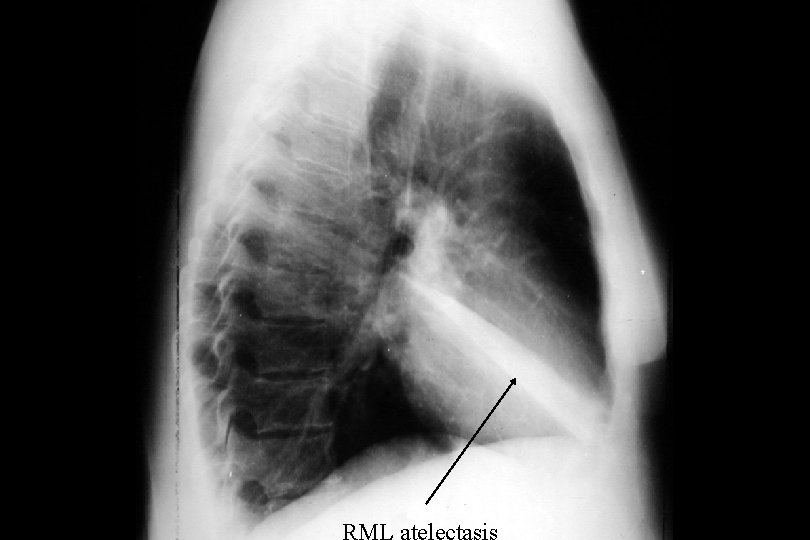

Azygous lobe RML atelectasis